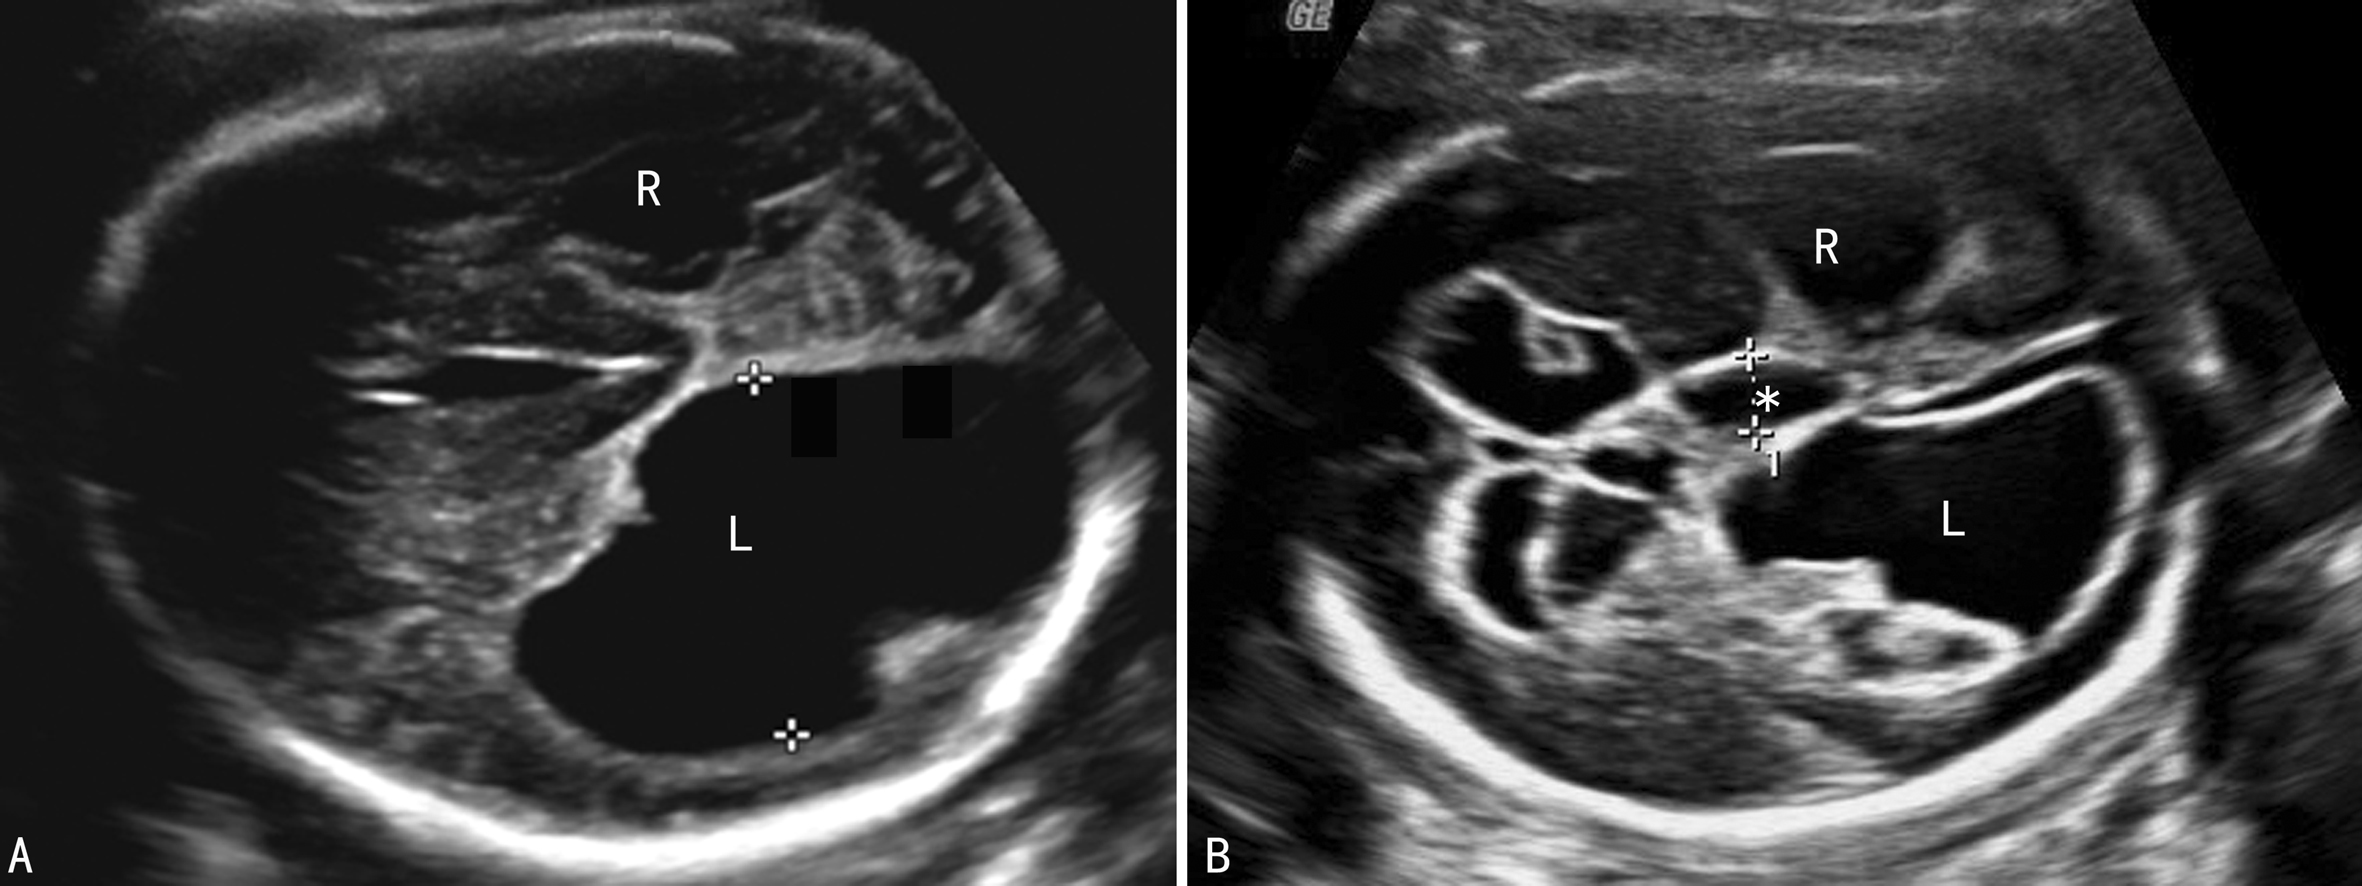

(1)单纯性脑室扩张(IMVM):可以是单侧或双侧(图1),3%~15%有染色体异常,通常为非整倍体异常,主要见于21-三体,在13-三体和18-三体中也常见,还可见于47XXY、47XYY、三倍体、染色体部分缺失、非平衡易位等。大多数IMVM可以自行缩小至正常范围,尤其是侧脑室宽度<13mm时自行消失的可能性很大,与CSF引流暂时性失调有关。McKechnie等报道有83%的轻型脑室扩张患儿可以正常发育,但困扰医生做出抉择或进一步检查的是有14%的IMVM会加重。因此,超声检查显示IMVM后仍需要进行系统的胎儿检查,仔细辨认有无伴发的其他异常、有无染色体异常的其他软指标。如果没有发现其他异常并且IMVM在分娩前消失的则有90%的胎儿预后良好,双侧不对称的IMVM(宽度差异>2mm)时预后不良,约一半的胎儿出生后有神经系统发育异常。侧脑室内径在10~12mm的预后优于内径13~15mm的胎儿。

图1胎儿双侧侧脑室扩张(TV第三脑室)

作为染色体异常的软指标,MVM合并染色体异常的风险性是3%~12.6%,单纯性MVM有4%的染色体异常的发生率,其预测价值在女性胎儿中可能比男性胎儿更大一些,最常见的是21-三体综合征(图2),其次为18-三体综合征、13-三体综合征、47XXY综合征、47XYY综合征、三倍体综合征、染色体部分缺失、非平衡易位等。不同的染色体异常引起的脑室扩张的原因可能有一些差异,但还不足以不同的脑室扩张区分染色体异常的类型。

图2 21三体胎儿脑不对称积水,第三脑室(*)扩张